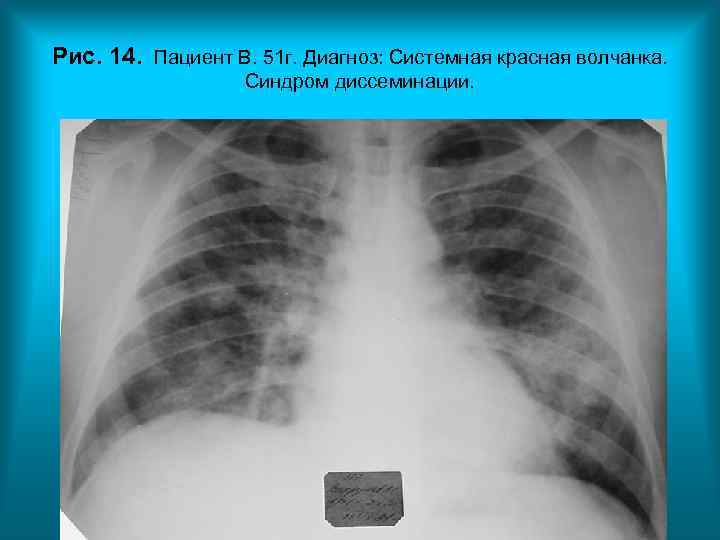

Рис. 14. Пациент В. 51 г. Диагноз: Системная красная волчанка. Синдром диссеминации. Н. С. Воротынцева. С. С. Гольев Рентгенопульмонология